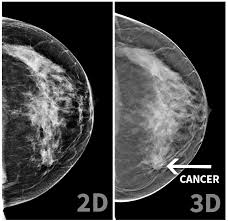

ÈéÏÙ°©µÄ¿ËÐÇ¡ª¡ªÐÂÒ»´ú3DÈé·¿X¹âÔìÓ°

3DÈé·¿X¹âÔìÓ°ÊÇÒ»ÏîÍ»ÆÆÐÔµÄÔìÓ°¼¼Êõ£¬Ô­ÀíÊÇ͸¹ýX¹âÏßÅÄÉãÈé·¿×éÖ¯£¬ÔÙ¾­ÓɼÆËã»úÖØ×éÁ¢ÌåÓ°Ïñ£¬ÒÔÁ˽âÈé·¿½á¹¹²¢Õì²ìÖ×ÁöºÍ΢¸Æ»¯µã¡£

³ÉÏñЧ¹û´«Í³2dÆ½ÃæÓ°Ïñ²»¹»ÇåÎú ÖØ×é³öÈé·¿ÇåÎúÁ¢ÌåÓ°Ïñ

׼ȷÂÊÑÇÖÞÅ®ÐÔÈéÏÙ×éÖ¯ÃÜ£¬Ò×ÖØµþ£¬Ó°ÏìÕï¶Ï׼ȷÂÊ£¬ÈÝÒ׳öÏÖ¼ÙÑôÐÔ»ò©ÕϲãÔìÓ°¸ÄÉÆÈéÏÙÖØµþµÄÈõµã£¬×¼È·ÂÊÌá¸ß40~51£¥£¬¿É²¶×½Î¢Ð¡¸Æ»¯µã

©Õï¿ÉÄÜÐÔ©Õï»úÂÊ0.9~6.5£¥Â©Õï»úÂʼ«µÍ

ÊæÊʸÐÊ®·ÖÍ´£¬ÐèÒª·´¸´¼·Ñ¹Èé·¿£¬Ã¿´Î10~20Ãë Ê¹ÓÃC-View¼¼Êõ£¬Ëõ¶Ì°´Ñ¹È鷿ʱ¼ä(ÿ´Î3.75Ãë)£¬±È2Dx¹â¼ÁÁ¿¼õÉÙ50%